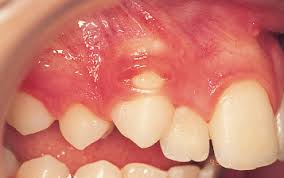

Window technique this represents the simplest form of open exposure. The open exposure technique consists of surgical removal of the tissue covering the tooth, leaving it exposed to the oral cavity. 26,27 in the case shown here, closed eruption was chosen for the impacted central and. Within the different approaches there exist two main options for the subsequent eruption of the impacted teeth (6): Open eruption technique the open eruption technique was the first method used to uncover impacted teeth.

Chaushu s(1), becker a, zeltser r, vasker n, chaushu g. Preorthodontic exposure and autonomous eruption The open exposure technique consists of surgical removal of the tissue covering the tooth, leaving it exposed to the oral cavity. Given the reported success of forced eruption, the technique requires… continue reading The present study provides information to patients and clinicians. Duration of surgical procedure (in min) click here to view Dr vanarsdall recommends open exposure with a repositioned gingival flap (pediculated connective tissue graft) above the impacted canine. Apically position flap the goal is to choose a technique that exposes the canine within the a zone of keratinized mucosa without involvement of the cementoenamel junction 27. The open eruption technique may be performed in two different ways, as described below. If the canine crown is positioned distal to the mesial aspect of the lateral incisor, an open technique is performed. Forced eruption can preserve the natural root system and related periodontal architecture, resulting in years of additional service for the patient. Open eruption through a window; In this technique sufficient space.